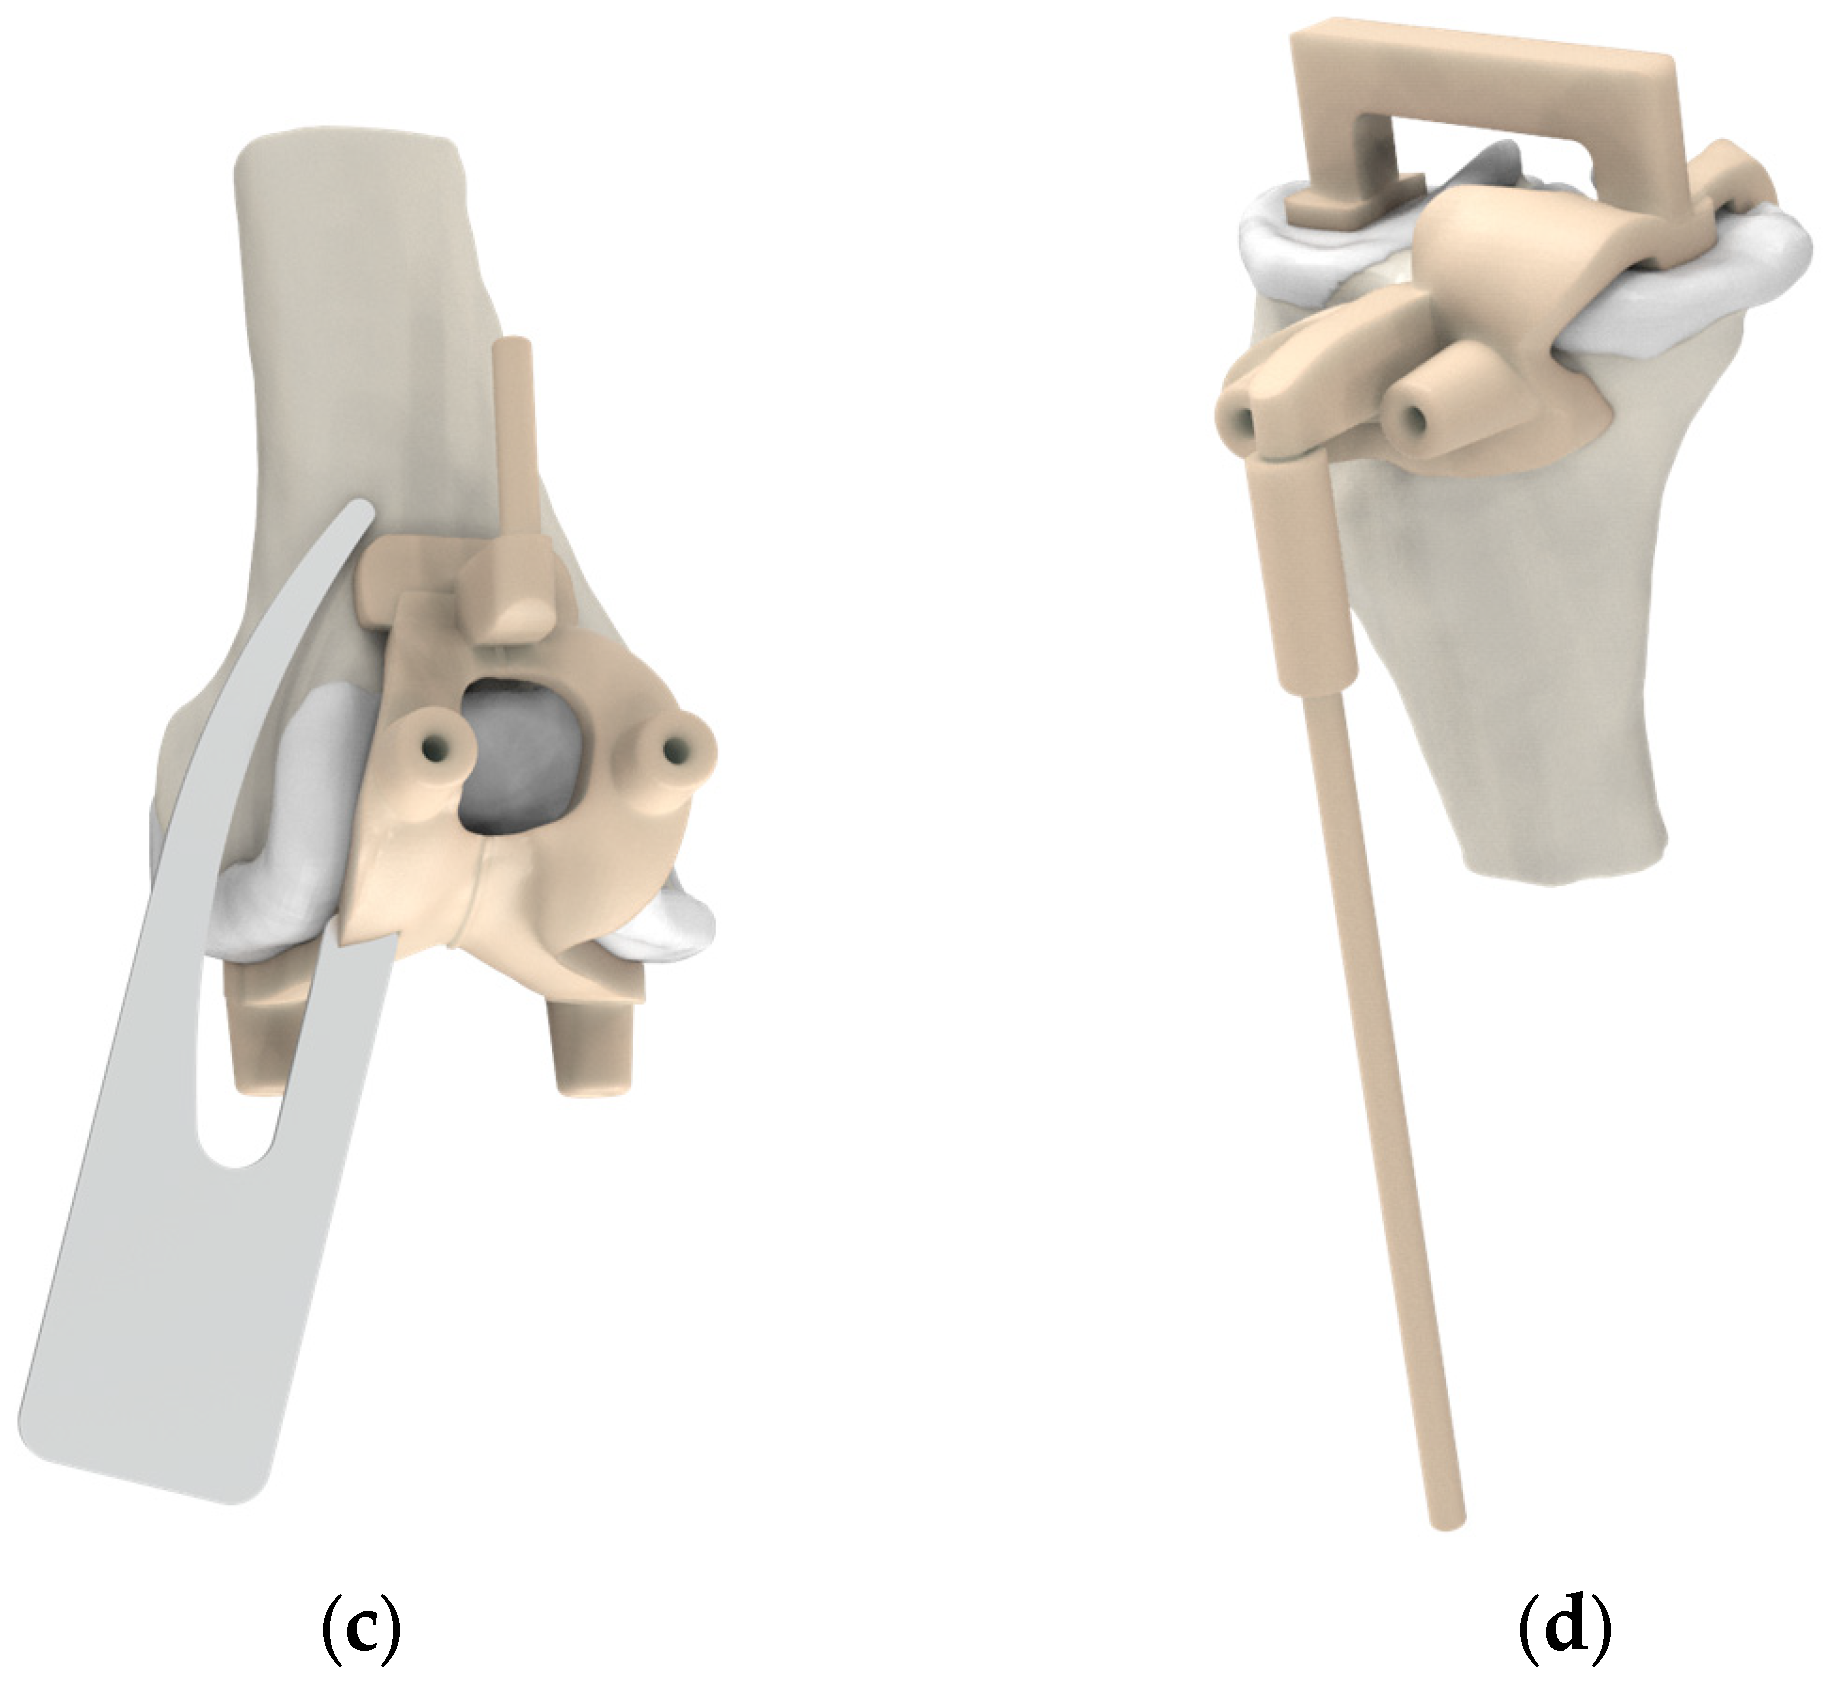

2.2. Pre-Planning and PSI Design Methods